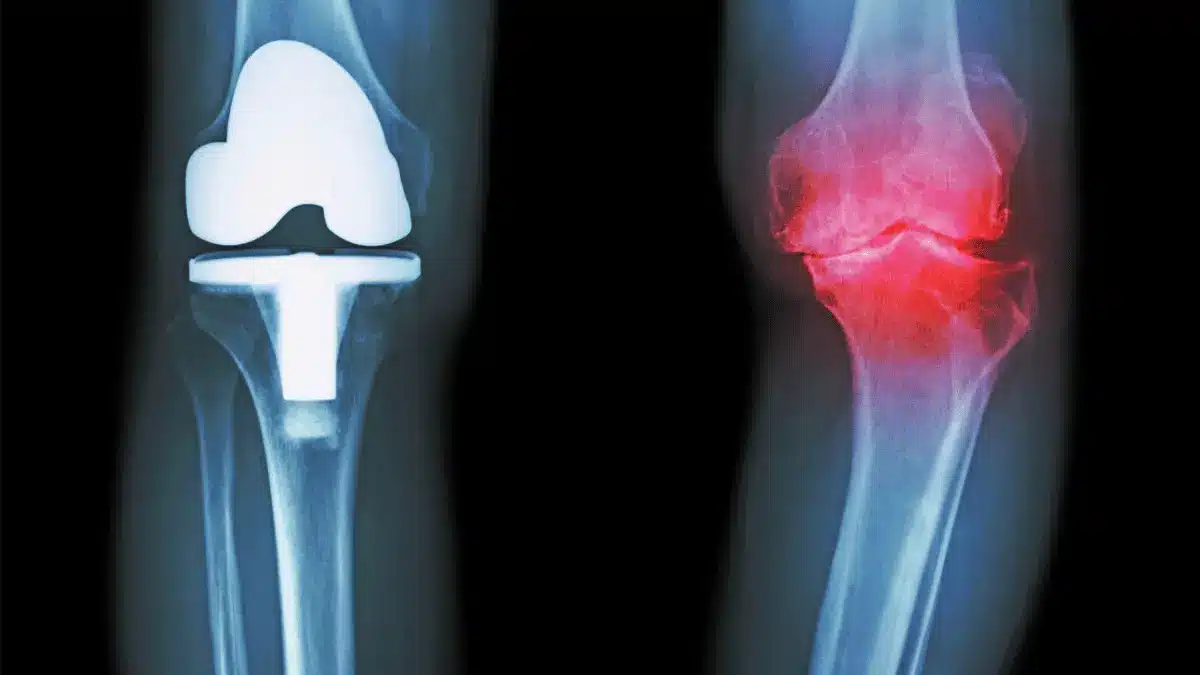

Prótese de Joelho

Tipos de Prótese de Joelho: Guia Completo e AtualMuitos pacientes chegam ao consultório com a seguinte pergunta: “Dr. Ulbiramar quais os tipos de prótese de joelho que existem?”… Leia mais »

Cirurgia de prótese de joelho: tudo o que você precisa saberA cirurgia de prótese de joelho é indicada para quem convive com dor persistente e limitação funcional por artrose avançada… Leia mais »